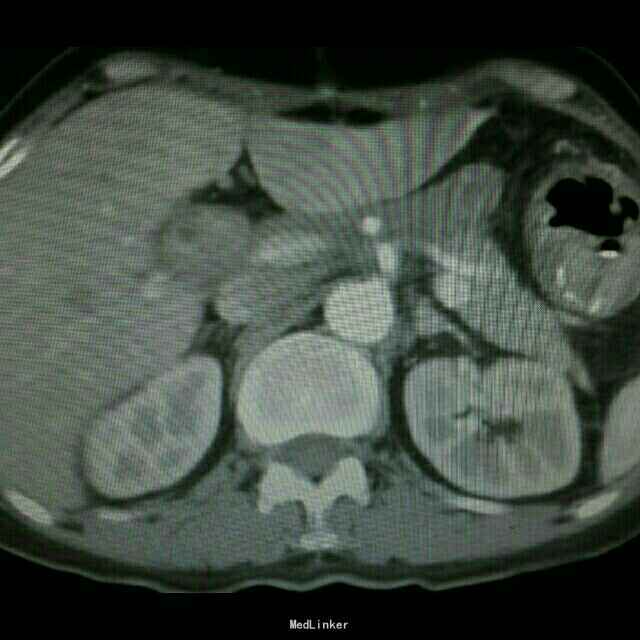

查体:入院后查体腹部平软,未见胃肠型,上腹部正中部可见20cm陈旧性瘢痕,腹部无压痛及跳痛,无肌卫;叩诊鼓音,肝脏及脾脏肋下未及;肝肾区无叩击痛,移动性浊音阴性,肠鸣音弱,1-2次/分。 检查:本次入院后查:WBC:9.2*10^9/L,Na:132mmol/L,余指标基本正常。电子胃镜:胃大部切除术后改变(毕II)吻合口粘膜充血水肿明显,直径约1.2cm,分别尝试进入输入袢及输出袢,见肠腔无明显狭;上腹部增强CT:1胰十二指肠切除术后;2肝脏多发小囊肿;3腹腔内未见明显感染及肿瘤转移征象。上消化道造影:残胃形态、扩张可,未见明显潴留液,蠕动较弱,中远部充盈不佳,胃小肠吻合口宽约1.2cm,未见狭窄及碘水渗漏。胃排空较慢。